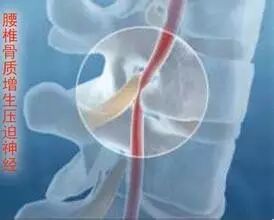

骨刺临床上称为骨质增生,多发于中年以上。这是因为随着年龄的增长,骨关节也会逐渐退化,当骨头与软组织接触的地方因长期承受压力、拉力、损伤,造成关节间的软骨渐渐失去水分与弹性,骨头与骨头磨损,人体为了减小骨关节之间的压力,在骨关节边缘上自然而然就会增生一部分来减少这个压力。它本质上是人体生理上的代偿功能,是人体为适应力的变化而产生的一种自我保护反应。

产生关节痛时,要及时到医院就诊,在医生指导下进行治疗和锻炼,绝大多数患者能够解除和缓解症状,并能减少和延缓骨刺的发生。只有当骨刺压迫了神经、血管,或关节严重疼痛、畸形、关节不稳定等影响日常生活和工作,保守治疗无效者才需要手术,黑百通痛可贴。